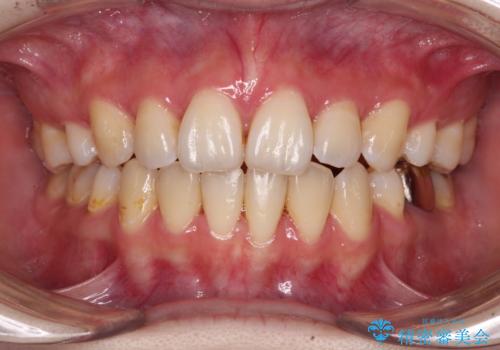

上下の八重歯とクロスバイト ワイヤー装置での抜歯矯正

- 八重歯とクロスバイトを気にして来院された患者様です。

上下ともに八重歯が顕著であり、前歯のクロスバイトがあったため、上下左右の第一小臼歯4本を抜歯し、ワイヤー装置での抜歯矯正を行うこととしました。

20歳ということもあり、歯の移動速度が非常に速く、1年強という短期間であっという間に治療を終えることができました。